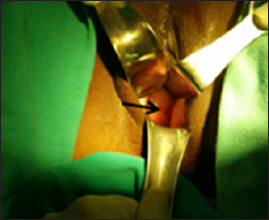

The mass appeared to be arising from anterior vaginal wall. A provisional diagnosis of anterior vaginal wall cyst was made and imaging studies performed. The ultrasound was suggestive of retention cyst (Figure 2). CT scan too pointed towards retention vaginal cyst (Figure 3). Since the diagnosis was not clear; the case was taken up for detailed examination under anesthesia, the mass was occupying the whole of vagina hence one could not go beyond the mass to locate the cervix, detailed per speculum examination under anesthesia revealed a small discolored spot (Figure 4) which when probed exuded tarry material (Figure 5). A diagnosis of cervical stenosis with retained blood was made and cervical opening was dilated to allow the collected blood to drain out. Appx 700 ml (Figure 6) of dark chocolate material was removed and cervix attained almost normal appearance and now the uterus could be palpated distinctly which appeared of normal size and shape. The lump abdomen had disappeared.

Figure 4: Discolored cervical opening being shown by arrow.